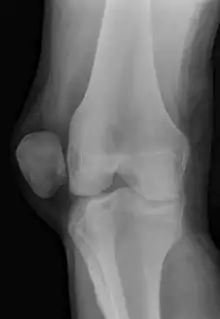

X-ray showing a patellar dislocation, with the patella out to the side.

A patellar dislocation is a knee injury in which the patella (kneecap) slips out of its normal position.[5] Often the knee is partly bent, painful and swollen.[1][2] The patella is also often felt and seen out of place.[1] Complications may include a patella fracture or arthritis.[3]

A patellar dislocation typically occurs when the knee is straight and the lower leg is bent outwards when twisting.[1][2] Occasionally, it occurs when the knee is bent and the patella is struck directly.[1] Commonly associated sports include soccer, gymnastics, and ice hockey.[2] Dislocations nearly always occur away from the midline.[2] Diagnosis is typically based on symptoms and supported by X-rays.[2]